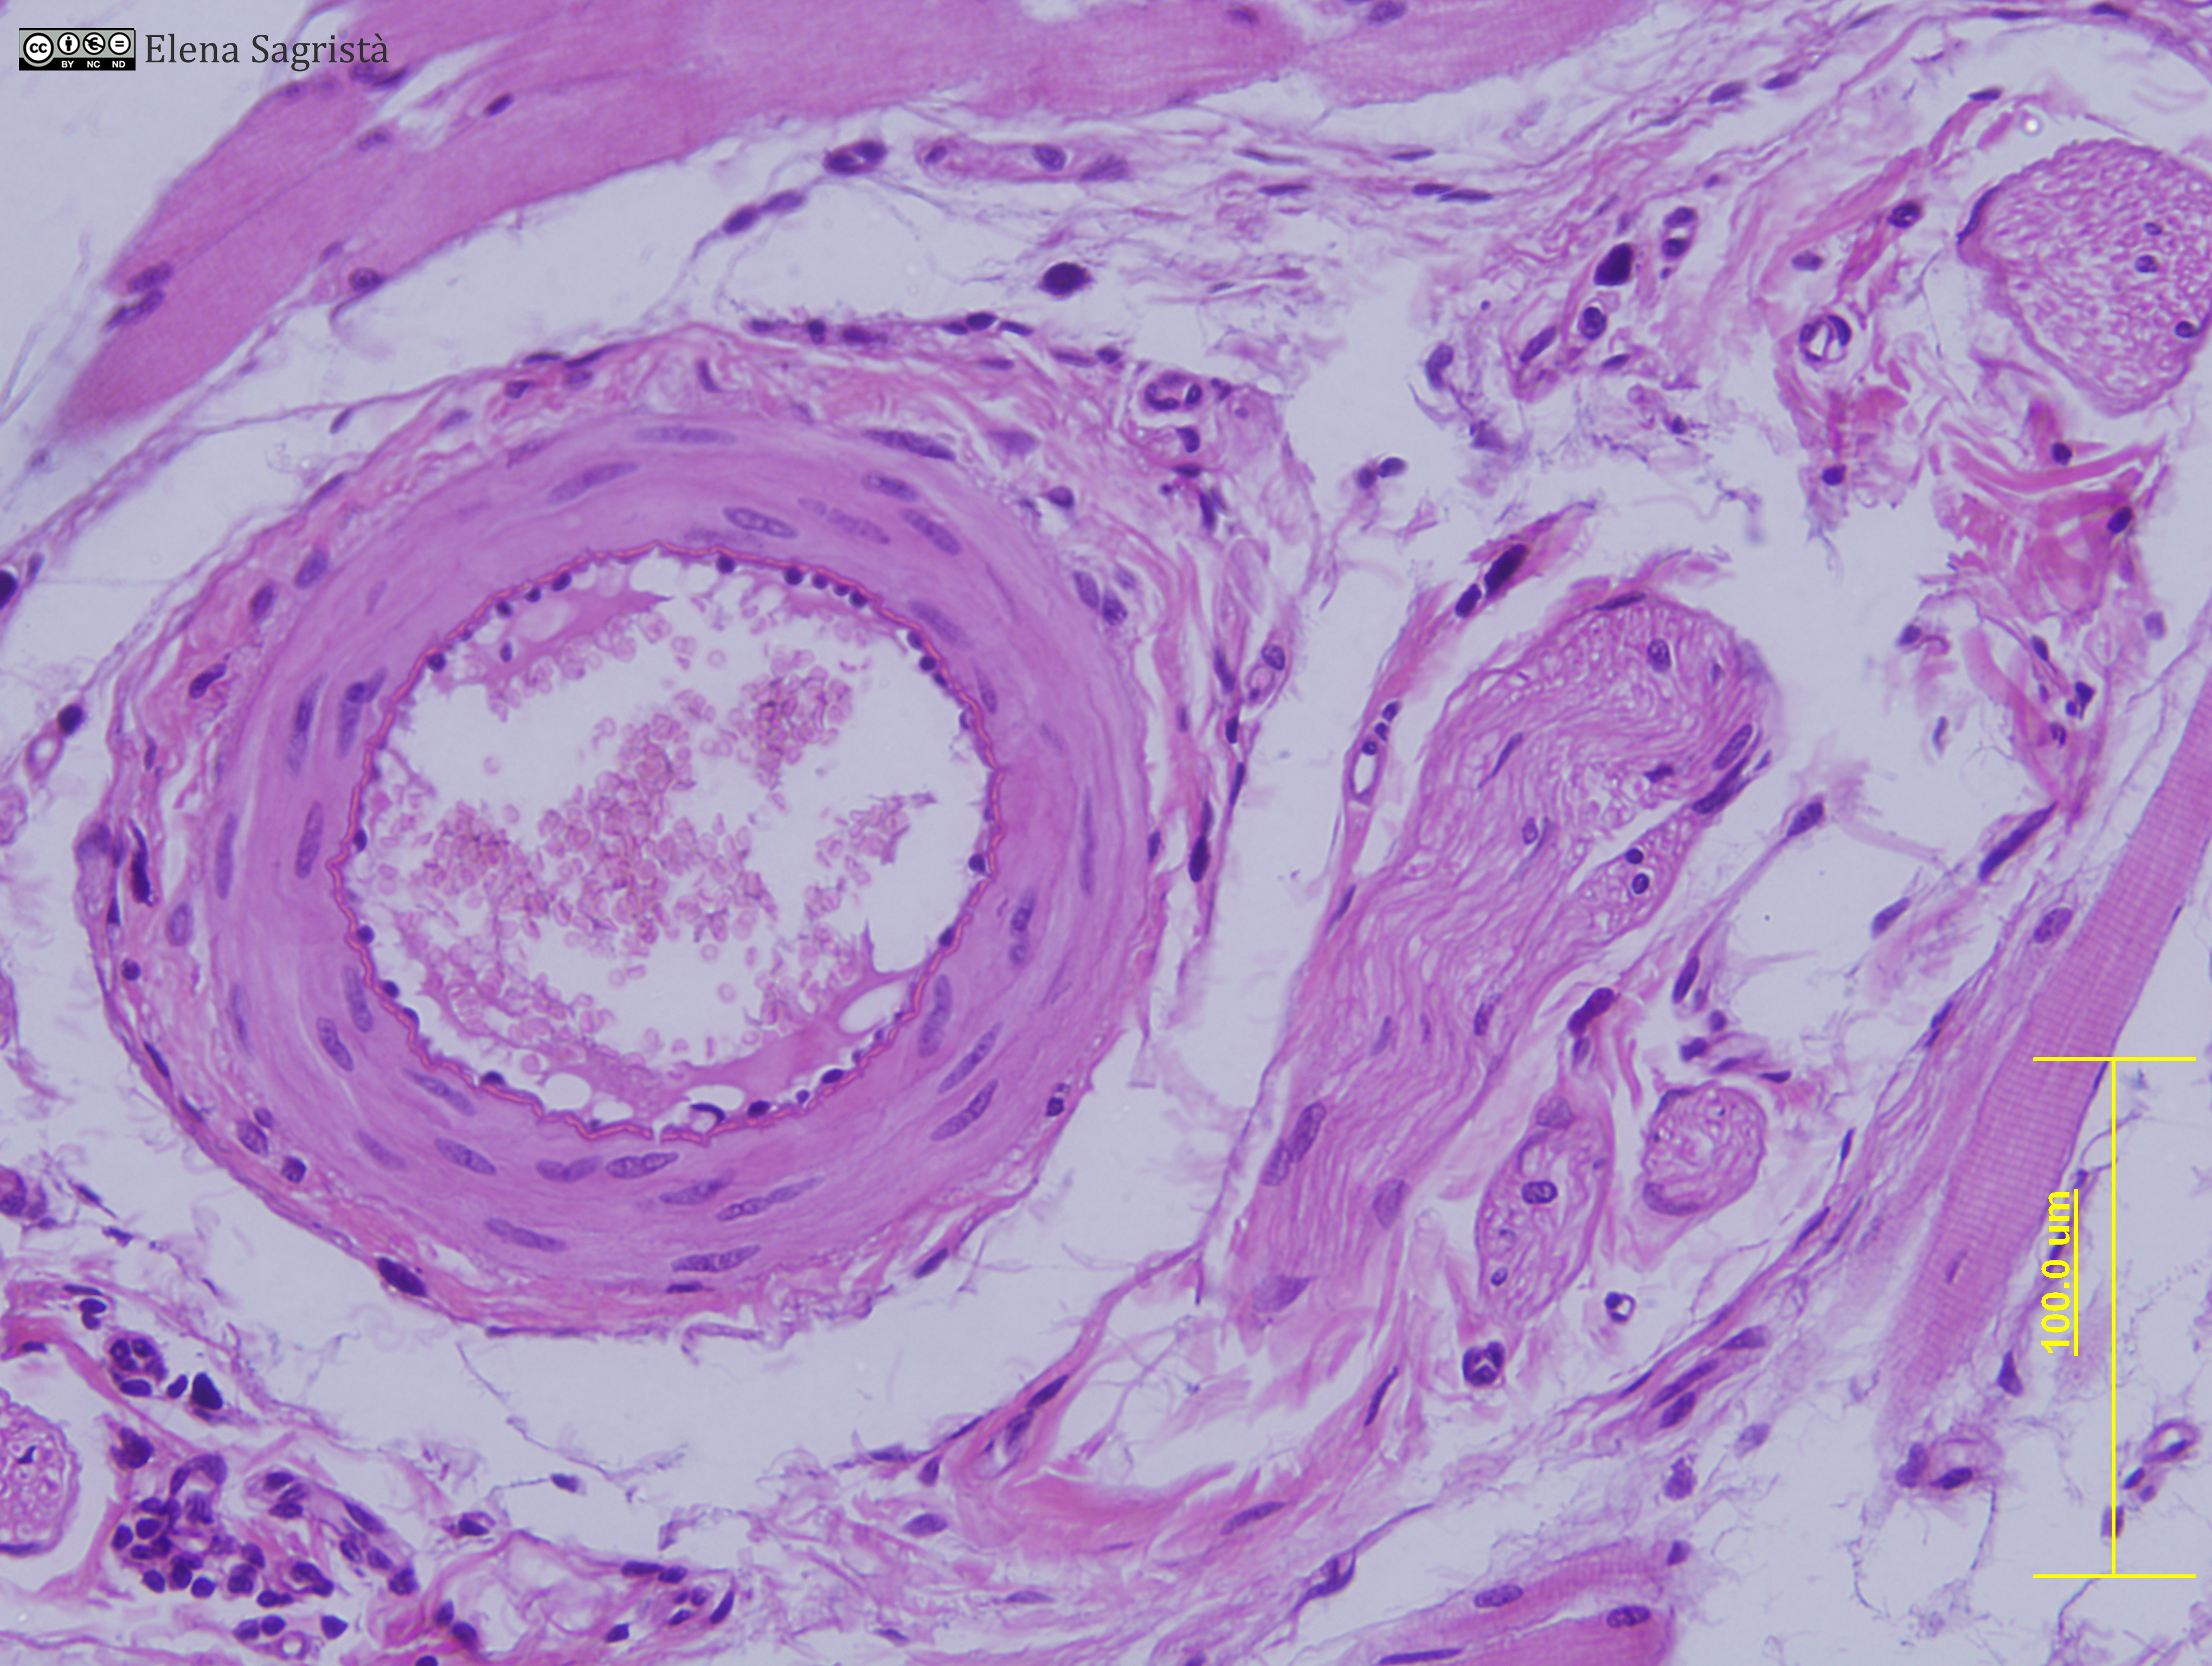

Histologia imatges: 10 Vasos sanguinis i limfàtics

Imatges de preparacions histològiques de Vasos sanguinis i limfàtics. Microscopia òptica.